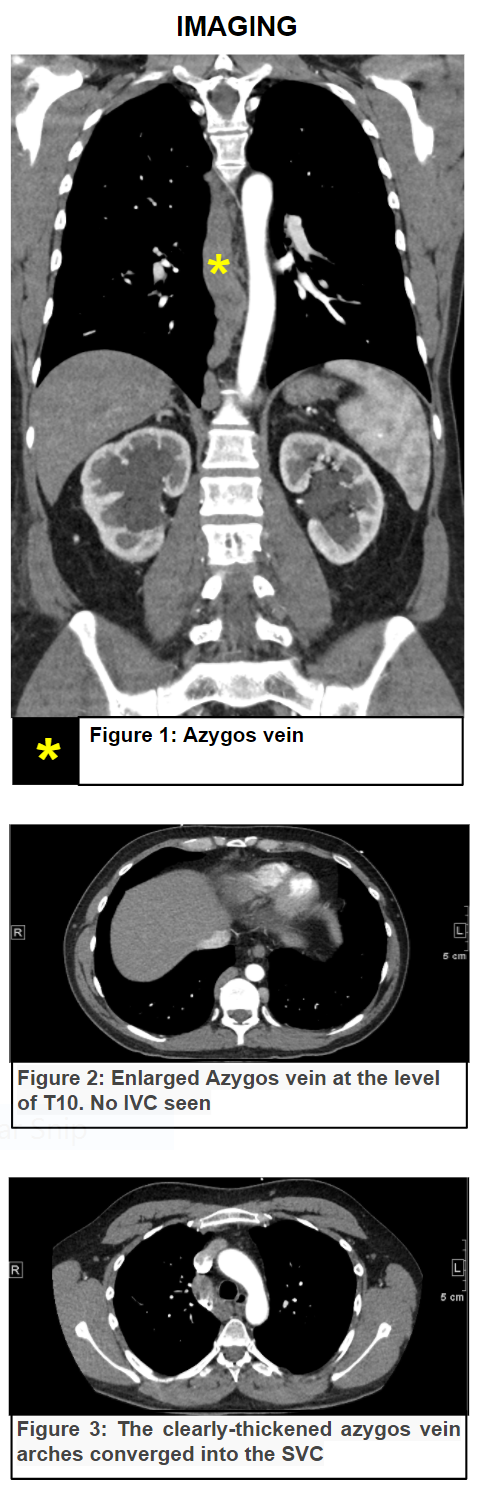

Case Presentation: Azygous continuation, an uncommon vascular anomaly that results from aberrant development during embryogenesis. It occurs in less than 0.6% of the population and may be associated with other congenital abnormalities. In adults aged between 20-40 years, the reported incidence is 10 times lower. With the increased use of different imaging studies such as HCT scan, MRI, and ultrasound these anomalies are being identified more often particularly in asymptomatic patients. Our patient is a 39-year-old gentleman who presented with worsening low back pain, bilateral lower extremity pain and swelling for 10-day duration. He was found to have “unprovoked” bilateral proximal DVT. The patient underwent CT of his chest and abdomen to evaluate his back pain. An Inferior Vena Cava (IVC) agenesis with azygous continuation incidentally discovered. The patient was successfully treated with anticoagulants and EKOS thrombolytic therapy was performed.

Discussion: Azygos continuation (AC) is a rare anomaly caused by the absence of the hepatic part of the IVC with blood flow to the Azygos vein, which joins the SVC in the right paratracheal space.

Clues for diagnosis are the presence of extensive and bilateral iliac thrombosis and an enlarged shadow of the azygos vein on chest X-rays. HCT scan and MRI are the gold standard modalities to diagnose IVC anomalies.